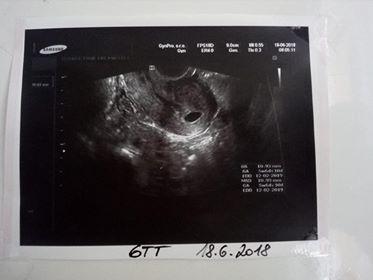

Takže děvčata...u doktora jsem byla a jelikož jsem poslední MS měla 12.5. tak mi vypočetl 6 týden. Říkala jsem mu o ovu testech a každotýdenních těhu testech a jen zvedl oči vsloup a neřekl na to nic. Můj DR. tam zrovna nebyl tak jsem chytla nějaký zástup. Jinak příští čtvrtek jdu pro výsledky ze stěru, bojí se, že bych mohla mít bakteriální výtok (který mě trápí snad od 14 let a snažím se s ním bojovat snad všemi existujícími způsoby). Tak jsem teď taková z toho nervózní...nevím co si myslet....jinak přidávám fotečku 🙂